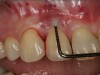

Probing is useful to determine the presence of biological complications at the buccal and lingual sites of implants, which cannot be evaluated on a radiograph (Figure 6 through Figure 8). Because of the absence of a periodontal ligament, bone loss on the buccal and lingual aspects of an implant indicates loss of support for the implant and may be a sign of additional circumferential bone loss around the implant.35

Fig 6. Periapical radiograph indicates proximal bone loss only.

Figure 6

Fig 7. Probing of the buccal surface reveals additional loss of attachment around the dental implant.

Figure 7

Fig 8. Flap elevation confirms circumferential bone loss.